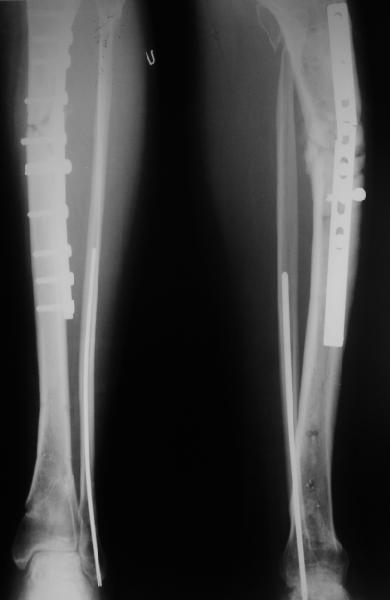

Выбран был вариант с удалением гвоздя и накостным остеосинтезом.

Прошло полгода, больная начала частично нагружать оперированную конечность, будучи в пластиковом ортезе и пользуясь 2 костылями.

Две недели назад появилась патологическая подвижность :-(

Вчера поступила к нам в отделение. Клинически определяется приличная подвижность, градусов 35 в переднезаднем направлении. На снимках еще видны фиксированная тоникм стержнем уже сросшаяся малоберцовая кость, и тоже сросшийя перелом дистального метадиафиза большеберцовой кости без признаков хирургической фиксации (?). Сегодняшний снимок также в приложении.

Планируем удаление пластинки и закрытый интрамедуллярный остеосинтез с рассверливанием.